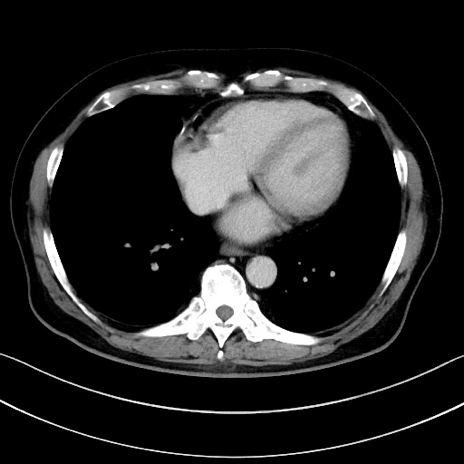

症例15(横断像)

【症例】70歳代男性

【主訴】腹痛

【現病歴】今朝から腹痛あり。全体的に痛い。特に左上の方。排ガスが今日はない。冷や汗が出る。

【既往歴】直腸癌術後

【身体所見】左側腹部〜上腹部に圧痛あり。腹膜刺激症状明らかなではない。軽度反跳痛。左下腹部に術後瘢痕あり。

【データ】WBC 7700、CRP 0.02